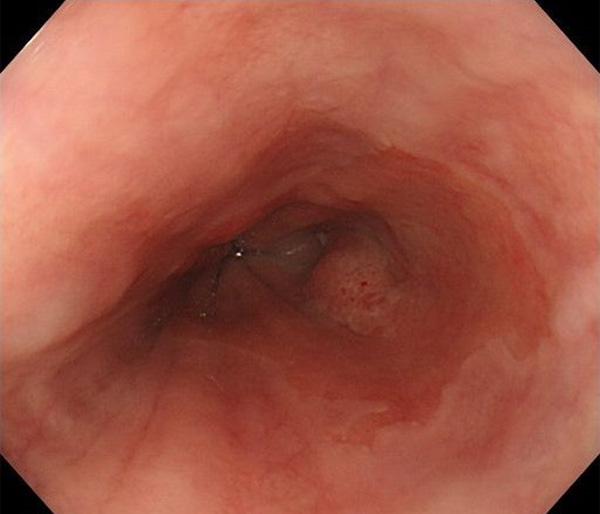

内視鏡所見と病理組織像の1対1対応が可能な症例を公募いたします。主にLSBEに発生した早期癌(HGDを含む)を対象としますが、興味深い症例であればSSBE癌でも結構です。採否は世話人へご一任ください。

特に、本邦では極めて稀なlong segment Barrett’s esophagus(LSBE)から発生した早期癌は、診断に難渋する場合も多く、欧米ではランダム生検による検出が標準的とされています。背景のBarrett食道もろとも全体を内視鏡切除+ラジオ波焼灼する欧米と異なり、ESDで内視鏡的な局所切除が基本の本邦では、存在診断+範囲診断(特に水平)を的確に行うことが不可欠です。

そのためには、一流の病理医による組織学的診断とエキスパート内視鏡医による拡大内視鏡像との一対一対応を徹底的に行うことで、『本来、見えないであろう拡大所見の先にある組織構築像が診えてくる』所まで内視鏡診断レベルを上げていく必要があります。その実現には、一対一対応を追究した症例(特にLSBE発生例)1例でも多く経験するしかありません。本研究会でBarrett食道腺癌(LSBE発生早期病変)を共に学び、拡大内視鏡像の一歩先を診るスキルを習得しましょう!一人でも多くの皆様のご参加をお待ちしています。

私は、Barrett食道癌はHGDも含め、内視鏡による存在診断、範囲診断が可能と信じて来ました。しかし最近、NBI拡大観察を併用しても側方範囲診断が不可能なLSBE症例を経験しました。診断技術を向上させるためには、多くの症例を診るしかありません。そこで、Barrett食道に造詣の深い先生方に世話人をお願いし、Barrett食道研究会を立ち上げることに致しました。全国からLSBE症例を集め、内視鏡的、組織学的診断に迫りたいと思います。皆様のご参加をお待ち致します。